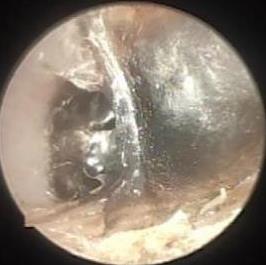

• 耳内镜下耳屏软骨-软骨膜鼓膜修补术后的短期疗效观察

摘要:目的 探讨耳内镜下耳屏软骨-软骨膜鼓膜修补术后的短期疗效。方法 回顾性分析2019年9月-2022年8月该院收治的78例鼓膜穿孔患者的临床资料,患者均采用耳内镜下鼓膜修补术。术后随访3个月,观察鼓膜形态和穿孔愈合情况,记录内镜图像、干耳时间、术前术后听力及耳鸣情况,以及外耳道狭窄等并发症的发生率。结果 术后3个月,鼓膜穿孔愈合率为97.44%(76/78),愈合良好,平均气导听阈较术前明显改善,气骨导间距较术前明显缩小,耳鸣较术前明显改善,差异均有统计学意义(P<0.05)。干耳时间为(4.21±1.12)周。术后出现肉芽5例,再穿孔2例,真菌感染2例,术腔感染、耳屏感染、外耳道狭窄和切口瘢痕各1例,所有患者术后均未发生面神经麻痹和感音神经性聋等严重并发症。结论 耳内镜下耳屏软骨-软骨膜鼓膜修补术是一种安全、有效的手术方法。根据术后愈合规律、内镜下鼓膜和外耳道形态特征,可为鼓膜修补术后正常中耳转归和并发症的诊疗,提供临床参考。